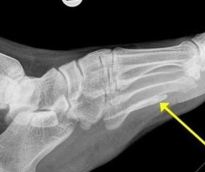

عثر أطباء على دودة طولها متر تقريباً مستقرة في قدم سوداني مهاجر مقيم في أستراليا، ظلت تتغذى على لحمه لأكثر من 4 سنوات. وشعر الرجل السوداني "38 عاماً" الذي توجه إلى ملبورن للاستقرار هناك، بتورم قدمه وكاحله بعد آلام استمرت معه لعام تقريباً، فزار الطبيب، ليظهر للأخير في الأشعة السينية التي أجراها المريض وجود دودة طولها متر، حسبما ذكرت صحيفة دايلي ميل البريطانية. وقام الأطباء بتحليل الدودة، فتبين أنها كانت مستقرة في منطقتي الكاحل والقدم على شكل قطعتين لولبيتين لأكثر من 4 سنوات، مشيرين إلى أنها ماتت بعدما تغذت على لحم القدم وبدأت في التحلل داخل جسم الرجل، محدثة له تورماً وقروحاً. وأوضح الطبيب المعالج د. داربي أن الدودة التي عُثر عليها هي "دودة غينيا" وهي دودة خيطية طويلة رفيعة تعيش تحت الجلد وتسبب قروحاً مؤلمة. يُشار إلى أن هذا النوع من الديدان موجود في جنوب السودان وإثيوبيا وغانا وتشاد، لكنها في الوقت ذاته ليست معدية، إذ لا تنتقل إلى شخص آخر.